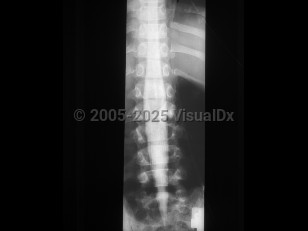

Diastematomyelia, split-cord malformation (SCM), is a rare congenital abnormality in which there is partial or complete cleft in the spinal cord by a sagittal osseous or fibrous septum. It is seen predominantly in females, most often affecting the lower thoracic or upper lumbar segments. Clinically, diastematomyelia often presents as tethered cord syndrome (back pain, abnormal gait, spasticity, bowel / bladder incontinence) in children or young adults, although symptom onset may occur at any age. Patients may have a midline cutaneous abnormality such as a hairy patch or dimple over the affected area. There are two classifications:

• SCM type 1 consists of two hemicords, each with its own dural sheath, separated by a bony or cartilaginous septum.

• SCM type 2 consists of two hemicords within the same dural sheath but separated by a fibrous septum.